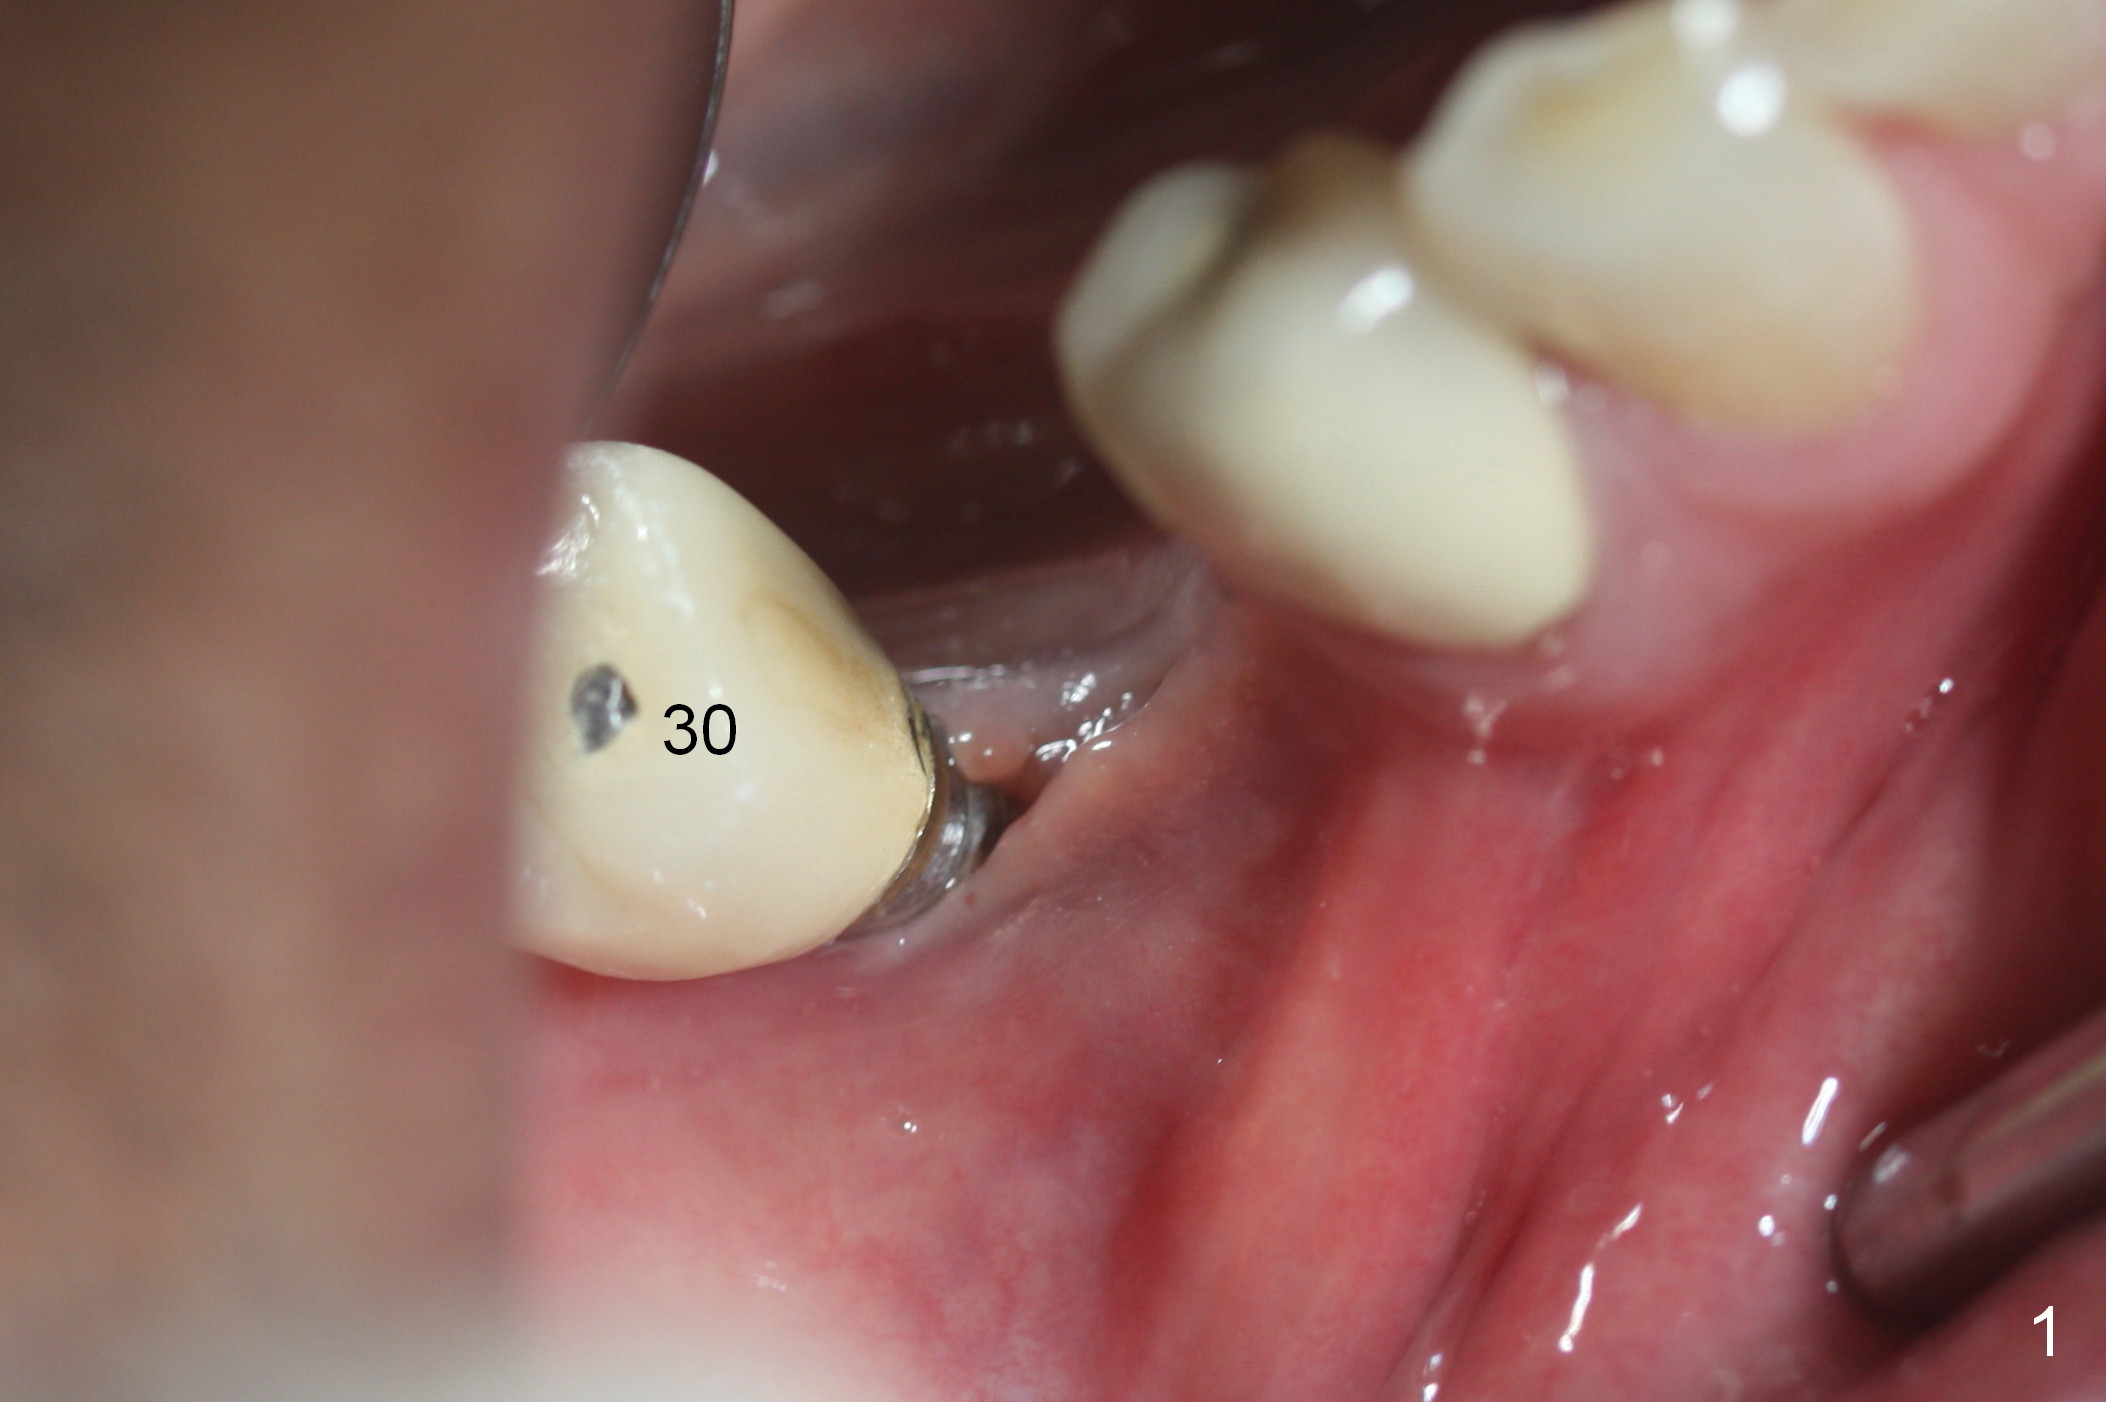

A 71-year-old man loses the implant at #29 five years post placement (Fig.1; 3 years post panoramic X-ray). The attached gingiva is nonexistent at #29 and 30. Gingival graft is necessary. The implant at #29 is placed as mesial (Fig.2) and lingual (Fig.5) as possible. If the implant at #30 is salvageable, place bone graft around the exposed implant threads (Fig.4,5 white circles). Cut a piece of 6-month collagen membrane, use a 4 mm tissue punch to punch 2 holes in the membrane (Fig.6 red circles) and cut open the hole for #30 lingually. Cover the membrane over the graft (Fig.5 red line), followed by PRF membranes (draw 5-6 tubes of blood).